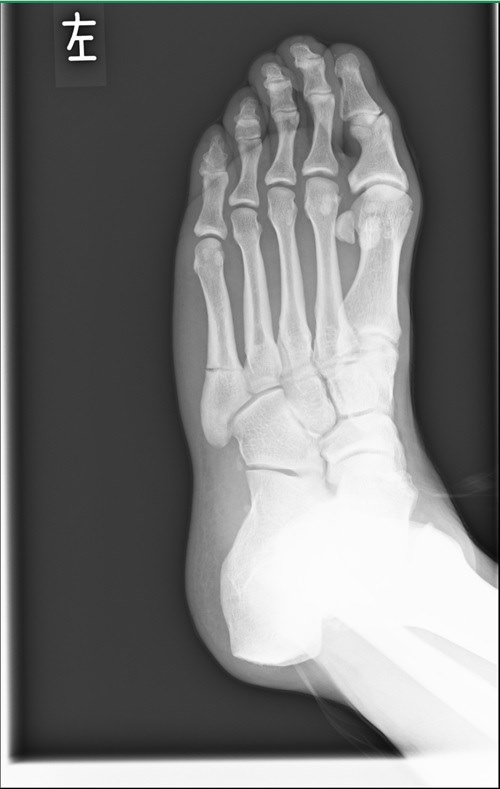

レントゲン 骨折して手術した右足 写真素材 フォトライブラリー Photolibrary